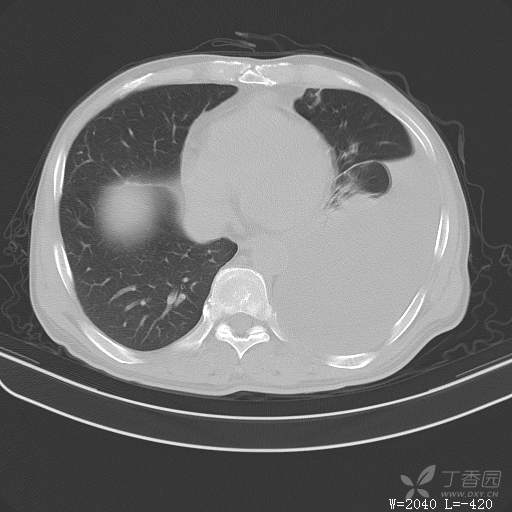

这个胸腔积液原因不寻常,大家猜猜看(得细心,这个很有意思)(俱乐部3)

简要病史:胸闷、憋气伴低热1月

体格检查:T:37.6℃;P:92次/分;R:20次/分;Bp:100/60mmHg,神清,呼吸平稳,周身未触及肿大淋巴结,右肺及左上肺叩诊清音,左下肺叩诊浊音,右肺及左上肺呼吸音粗,左下肺未闻及呼吸音,心率92次/分,律齐,无杂音。腹部平坦,软,全腹无压痛,无反跳痛及肌紧张,肝脾肋下未触及,双下肢无水肿。

辅助检查:白细胞数目4.41 × 10^9/L,中性粒细胞百分比82.1%,*血红蛋白111g/L,*血小板数目91 × 10^9/L,凝血四项:凝血酶原时间12.5秒,国际标准化比值1.07,活化部分凝血酶原时间36.1秒,纤维蛋白原浓度6.52g/L,肾功能示:肌酐47.4umol/L,尿酸150umol/L,电解质示:钠133.5mmol/L,D-二聚体0.88mg/L,血沉67.71MM/H,C-反应蛋白114.6mg/L,肝功能:*总蛋白49.6g/L,*白蛋白27.4g/L,查胸水常规及胸水生化提示渗出液,胸水ADA154U/L,查胸水病理未见肿瘤细胞。超声:腹膜后有3~4枚肿大淋巴结,直径1~1.5厘米,余浅表淋巴结不大。

临床诊断:左侧胸腔积液

治疗经过:胸水引流。胸水白蛋白23.8克/升,乳酸脱氢酶275单位/升,胸苷激酶182单位/升,胸水外观黄色混浊,总细胞4320个/微升,白细胞4320个/微升,单核细胞80%,多核细胞20%。考虑结核性胸膜炎,结果查肿瘤标志物、胸水细胞学阴性,胸水TB—DNA阴性,结核菌素试验+,结核抗体阴性,TB-SPOT阴性,胸膜活检阴性。怎么办?

大家猜猜胸水原因是什么?